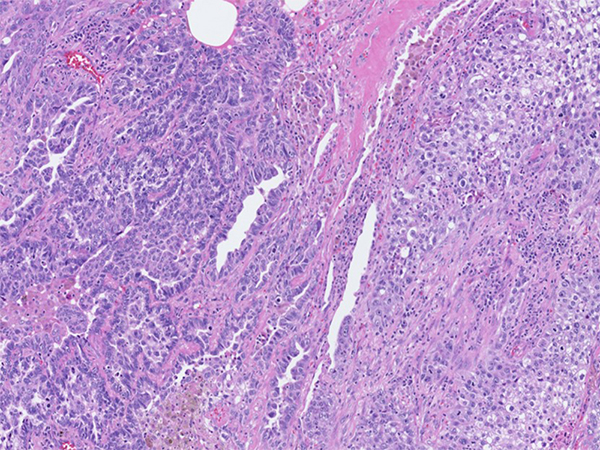

Clinical History: A 73-year-old man was seen in the emergency room for neck and cheek swelling, which turned out to be a blocked salivary duct which eventually resolved. During this visit, it was noted that he had a right upper lobe lung lesion on chest CT imaging. He was a firefighter and continued to smoke a half a pack per day for the last 25-30 years. Later, he underwent wedge resection (Figures 1-3 H&E, 4-7 TTF-1/p40) followed by completion lobectomy of the right upper lobe of lung.

Positivity for TTF-1 in malignant glands and p40 in the solid component supports the diagnosis of adenosquamous carcinoma.